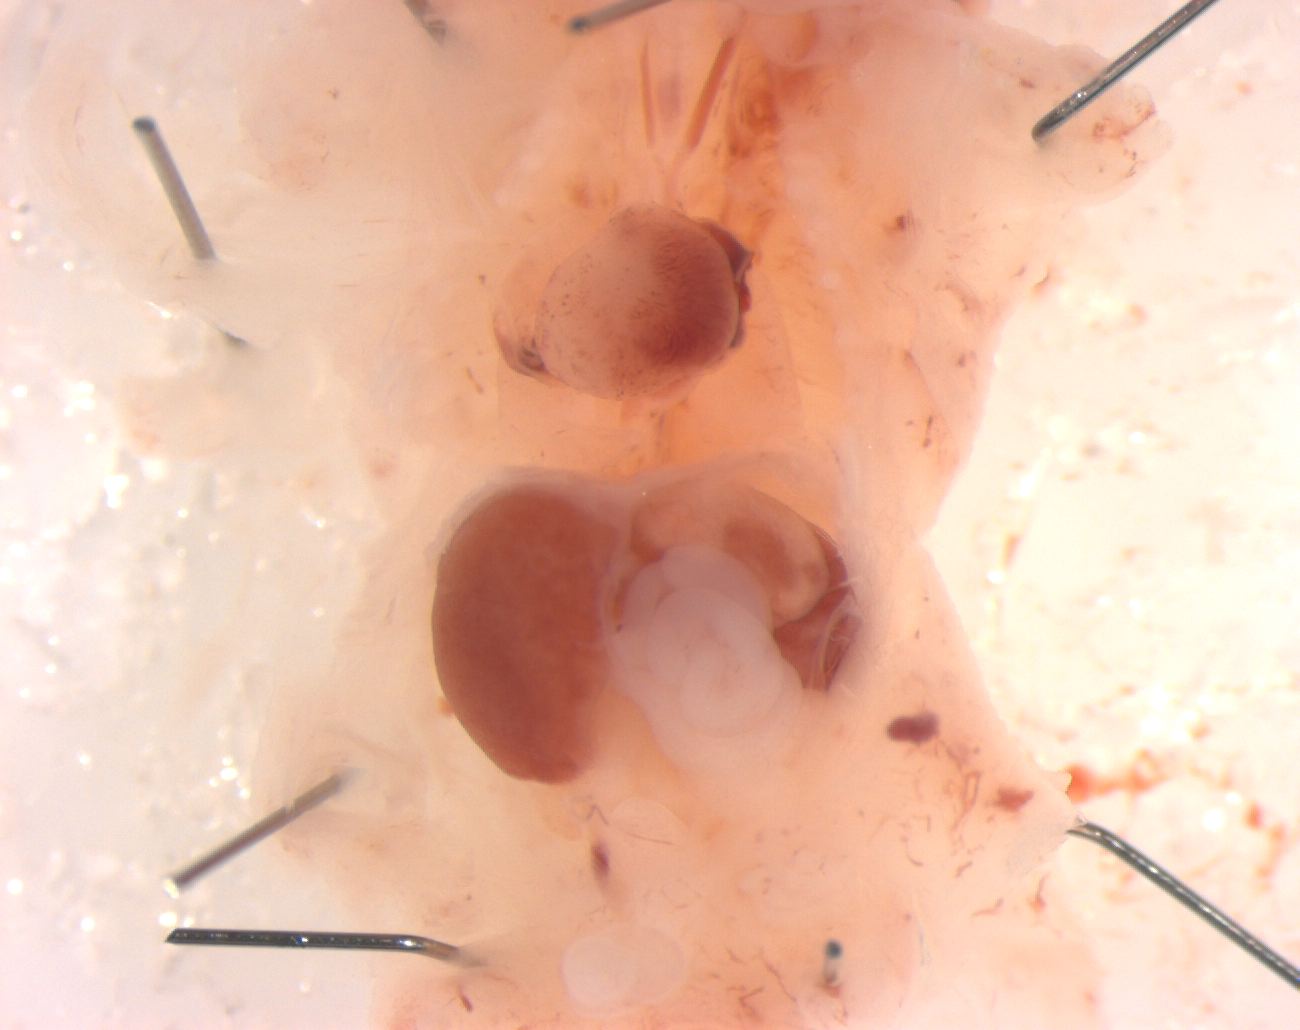

Caption Mutant 1735-003-1 presents with heterotaxy indicated by dextrocardia and dextrogastria

Ccdc39b2b1735Clo coiled-coil domain containing 39; Bench to Bassinet Program (B2B/CVDC) mutation 1735, Cecilia Lo

Ccdc39b2b1735Clo/Ccdc39b2b1735Clo C57BL/6J-Ccdc39b2b1735Clo